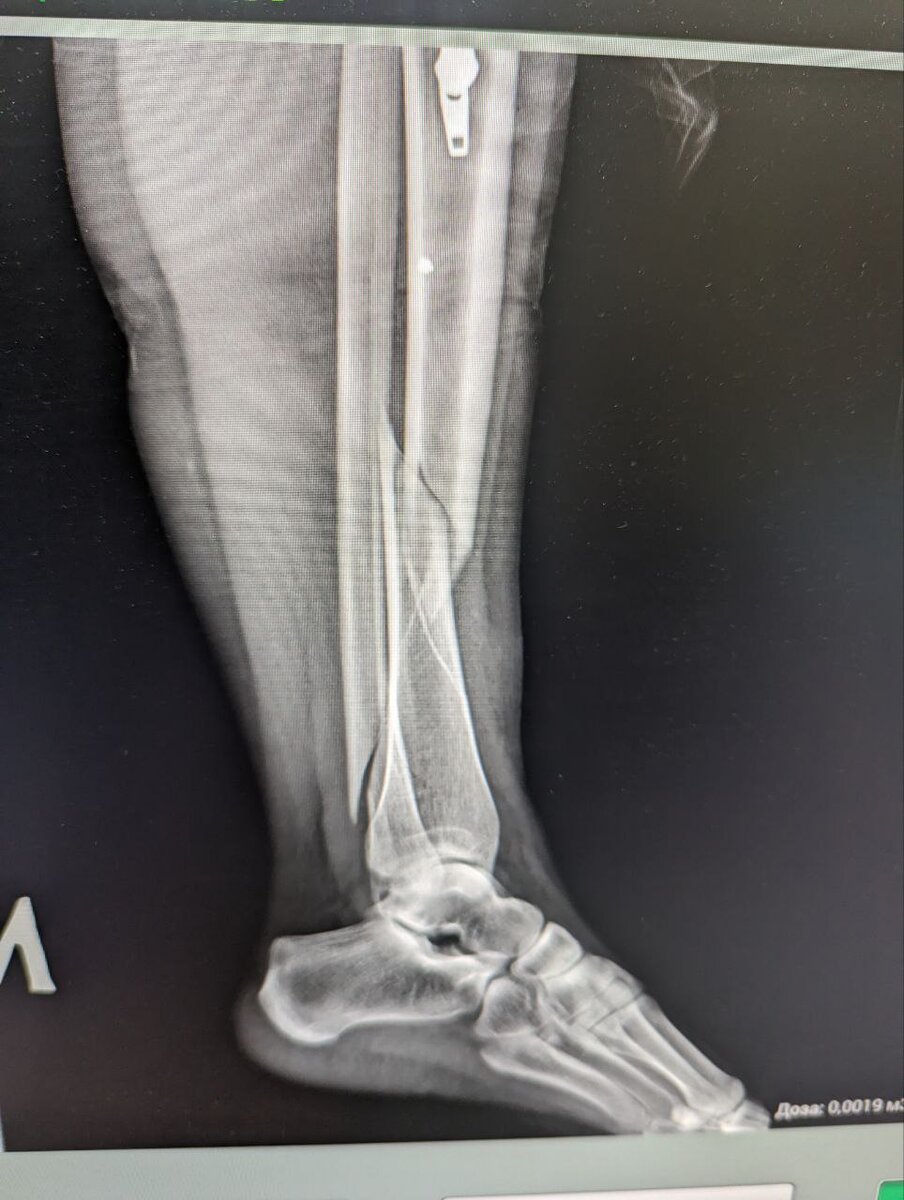

мой переломчик

Так получилось, что в ноябре 2023 года мы купили билеты в Таиланд. Кто же знал, что 5 января, я выехав на 15 минут покататься по замерзшей Ладоге в Карелии на горных лыжах за снегоходом - сломаю ногу, серьезно так сломаю, с операцией и вживлению металла в ногу.